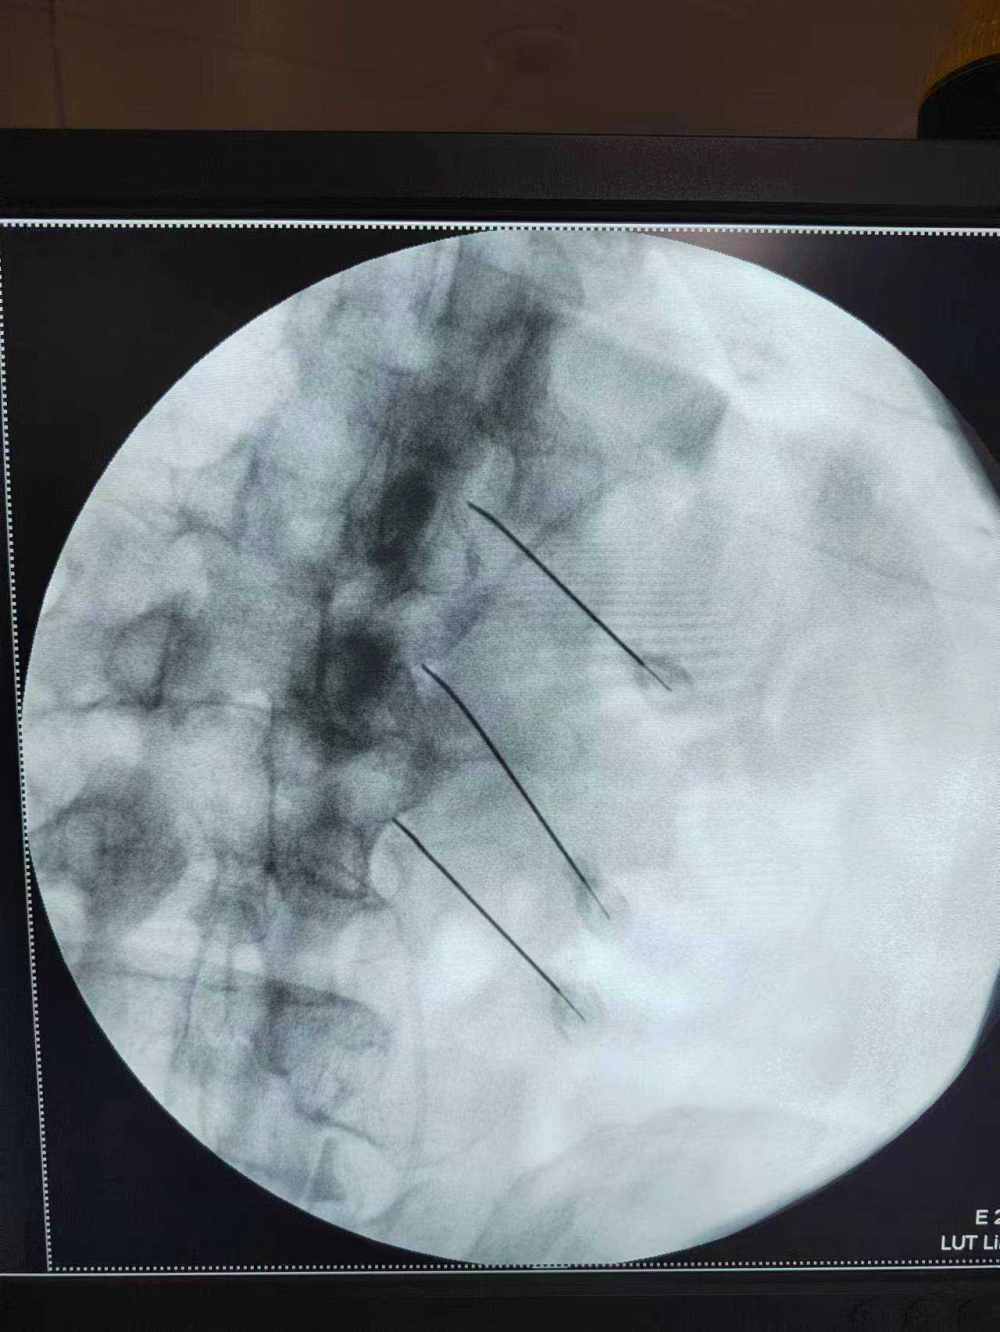

患者徐×軍,82歲,三個(gè)月前不明原因全身刀割樣疼痛,觸摸時(shí)加重,飲食、睡眠、行走均受影響,雙下肢肌肉萎縮,以致只能依靠坐輪椅生活,雖輾轉(zhuǎn)多家醫(yī)院治療效果不佳,排除腫瘤等重大疾病。7月7日,抱著試試看的心理來到我院疼痛科住院。主治醫(yī)師常斌接診后,對(duì)老人狀況非常同情。分析病情后,立即制定治療方案,為早一點(diǎn)減輕老人痛苦,加班給老人做了脊神經(jīng)后內(nèi)側(cè)支的射頻治療。2天后又給予右膝關(guān)節(jié)的膝神經(jīng)阻滯治療。治療后,病情明顯好轉(zhuǎn)。

射頻治療是在影像學(xué)引導(dǎo)下,在局麻后將直徑僅0.7毫米射頻針穿刺入靶點(diǎn)治療區(qū)域(如神經(jīng)根、神經(jīng)節(jié)、椎間盤等),針對(duì)病變部位進(jìn)行射頻熱凝或脈沖射頻,起到神經(jīng)調(diào)節(jié)或熱凝固作用,從而治療疼痛。